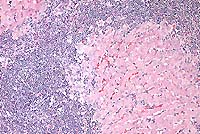

Contributor's Diagnosis and Comments: Enteritis, granulomatous, diffuse, chronic, severe, with diffuse granulomatous lymphadenitis and multifocal lymphogranulomatous phlebitis, lymphangitis and arteritis, mixed breed, adult ovine, caused by acid-fast bacilli, Mycobacterium avium var paratuberculosis, Johne's Disease.

In this case, there is extensive atrophy of normal mucosal

components, which are replaced by an extensive infiltrate of macrophages

into the lamina propria and submucosa, and also with variable

numbers of lymphocytes, plasma cells, neutrophils and eosinophils,

and generally low numbers of Langhans giant cells and epithelioid

macrophages. Peyer's patches are hyperplastic, and mesenteric

attachments are edematous. There are nodular areas of vasculitis

and lymphangitis (not present in all sections). Although the surface

epithelium is absent in most areas, this is interpreted as an

artifact associated with autolysis and not an ulcerative process.

The macrophages throughout the intestinal lesions are distended

with mycobacteria, confirmed by Ziehl Nielsen stains, but apparent

as fine basophilic cytoplasmic stippling in H&E-stained sections.

The lesions are typical for the so-called lepromatous or multibacillary

form of ovine Johne's disease (JD). A second form of the disease

in small ruminants, the paucibacillary form, has few organisms,

few infected macrophages and the inflammatory lesions are predominantly

lymphocytic rather than granulomatous. In this second form, the

diagnosis may be difficult to confirm, either by histopathology

or by culture.